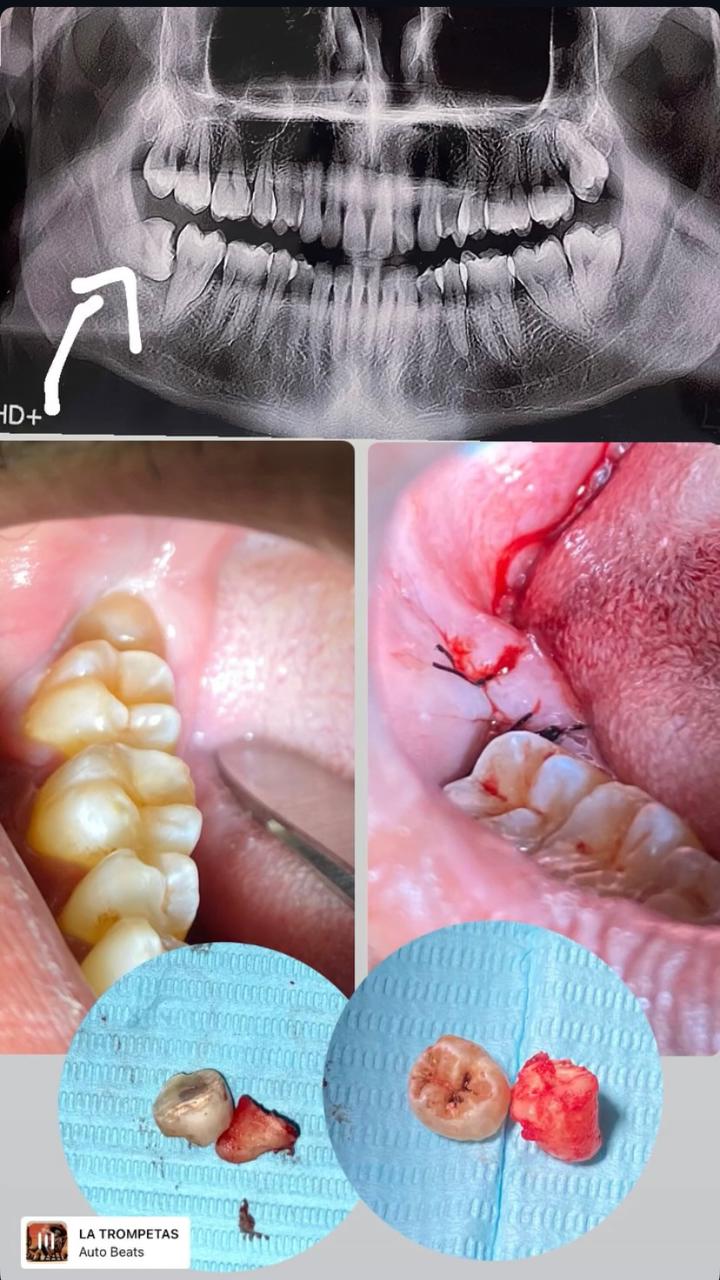

جراحة الأسنان